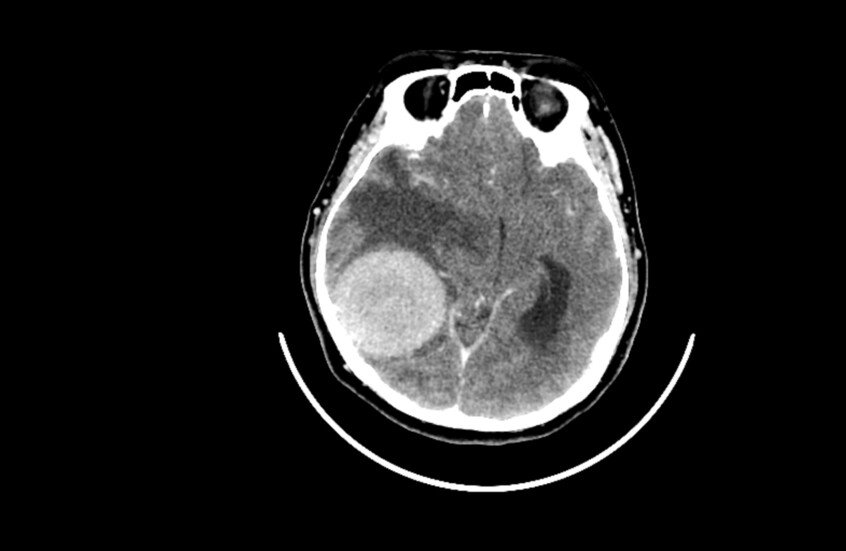

دراسة صادمة.. القلق والدوار يرتبطان بأورام الدماغ!

توصلت دراسة حديثة إلى وجود علاقة بين القلق والدوخة من جهة، والأورام الدماغية الحميدة من جهة أخرى.